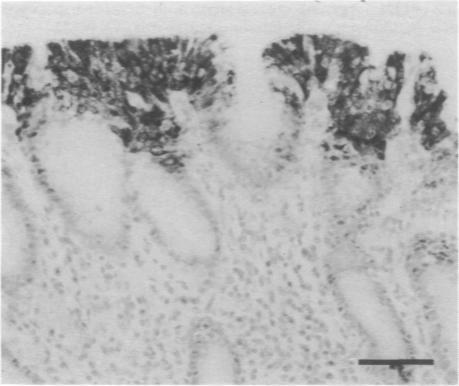

Epidermal growth factor (EGF), its related peptide transforming growth factor (TGF-alpha) and their common receptor (EGFR) have been implicated in the control of cell proliferation and differentiation in the gastrointestinal epithelium and may play an important role in gastric carcinogenesis. We compared the immunohistochemical expression and topographic distribution of these peptides using Western blot analysis in gastric carcinoma precursor lesions and in non-cancer tissue. We observed: (i) increased and extended expression of TGF-alpha in normal mucosa and hyperplasia in carcinoma fields compared with non-cancer controls; (ii) increased expression of EGFR in intestinal metaplasia (IM) from carcinoma fields compared with controls; (iii) EGF expression was not detected in normal mucosa and only weakly in IM; (iv) coexpression of TGF-alpha/EGFR and EGF/EGFR was higher in intestinal metaplasia in carcinoma fields than in non-cancer controls. We conclude that altered expression of TGF-alpha/EGFR is associated with morphological changes during gastric carcinogenesis. In this regard increased expression of TGF-alpha is a very early event which is subsequently followed by up-regulation of EGFR and this has important biological and clinical implications.